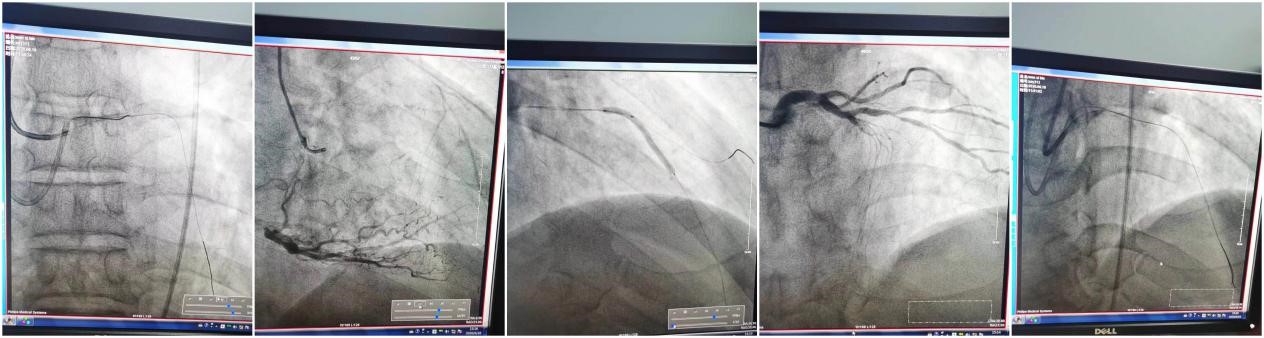

我院自2019年6月1日成立胸痛中心,由急诊科、心内科、介入科等多学科组成,为胸痛患者提供快速而准确的诊断、危险评估和及时有效的治疗手段,提高胸痛患者早期诊断和治疗能力,缩短救治时间,减少误诊和漏诊,降低胸痛患者的死亡率,改善临床预后。胸痛中心运行以来,郑崔成医生兼任胸痛中心医疗总监,每天忙碌的他常常被同事们打趣道,他就是西游记里会七十二变的孙悟空,是古时的文武状元,文武兼全。前一刻他还在病房抢救、查房,忙碌着书写病案,随后却转战导管室,在无眠的长夜中,身穿铅衣,手持导丝,全神贯注地定位、穿刺、送导丝、扩球囊、放支架。

在全力抗击新冠肺炎疫情期间,他完成了两次技术性、突破性手术,其中一例是逆向进攻开通对侧慢闭病变,历经4个半小时,分别开通前降支、回旋支,在闭塞病变处各植入支架1枚,患者生命体征平稳,疼痛减轻;另一例是双指引导管同时进入左主干,进行前降支闭塞介入治疗,予以逆行造影,开通闭塞病变,开通后涉及两个分叉病变,利用双指导,双轨道完成手术,成功植入2枚支架完成闭塞血管的开通,恢复了患者的生命线!